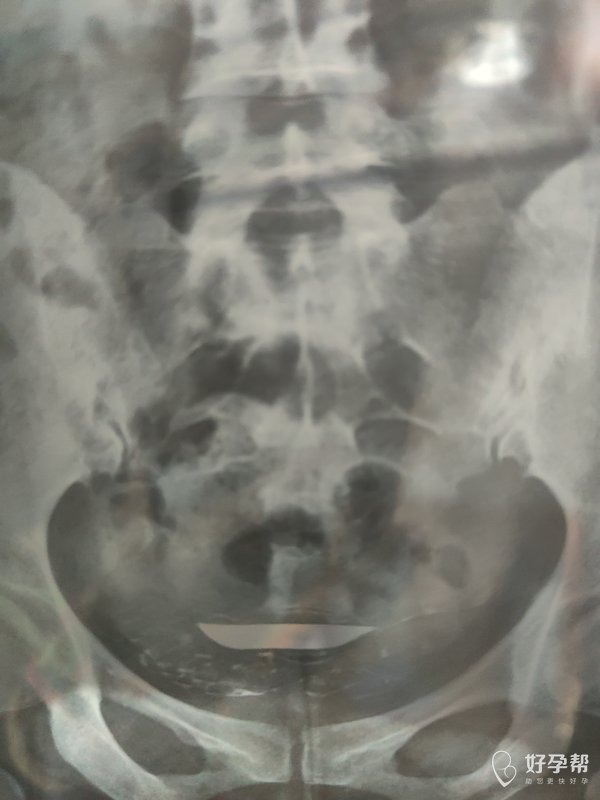

各位医生好前天做了输卵管造影请帮忙看看这些造

双侧输卵管通畅,弥散好,正常造影,可以试孕。